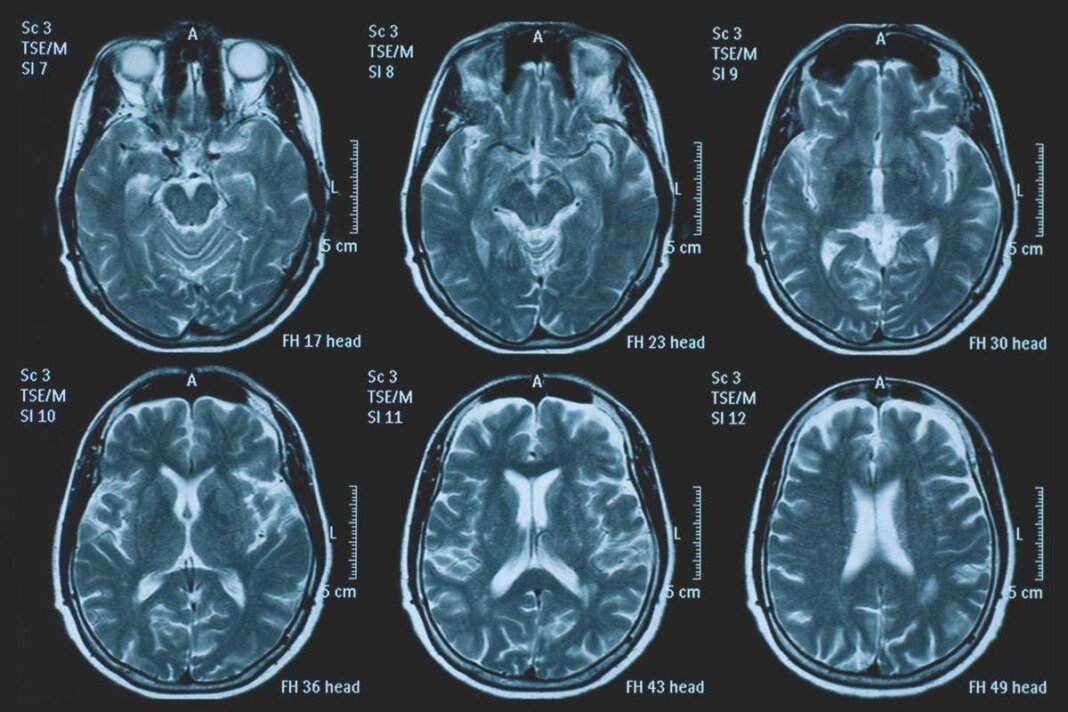

(Adnkronos) – La Commissione europea (Ce) ha autorizzato la commercializzazione condizionata di tovorafenib come monoterapia per il trattamento dei pazienti di età pari o superiore a 6 mesi con glioma pediatrico di basso grado che presentano una fusione o un riarrangiamento del gene Braf o una mutazione Braf-V600, in progressione di malattia dopo una o più terapie sistemiche precedenti. Lo annuncia Ipsen, in una nota, precisando che si tratta della “prima terapia mirata” per questa patologia e che la decisione della Ce si riferisce ai 27 Stati membri della Ue, oltre a Islanda, Liechtenstein e Norvegia. Ogni anno in Ue vengono diagnosticati più di 800 nuovi casi di glioma pediatrico di basso grado (pLgg) con alterazione di Braf. Questo tumore cerebrale, nonostante sia classificato di basso grado (a lenta progressione), comporta un carico significativo e permanente che accompagna la persona per tutta la vita, causando spesso importanti compromissioni fisiche e neurologiche, tra cui perdita della vista, difficoltà di linguaggio e disfunzioni motorie, che possono incidere in modo significativo sull’istruzione, l’autonomia e la qualità di vita a lungo termine del bambino. Finora, molti bambini con pLgg hanno dovuto sottoporsi a interventi chirurgici invasivi, a più cicli di chemioterapia e a radioterapia, con conseguenti complicazioni della salute.

L’approvazione della Ce si basa sui dati dello studio di fase 2 Firefly-1 che ha valutato tovorafenib in 137 bambini e giovani adulti con pLgg recidivato o refrattario con alterazioni di Braf che avevano ricevuto almeno una precedente terapia sistemica. Nel dettaglio, lo studio ha dimostrato una risposta tumorale clinicamente significativa con un tasso di risposta globale del 71% secondo i criteri Rano-Hgg (ResponseAssessment in Neuro-Oncology criteria for High-Grade Gliomas) e del 53% secondo i criteri Raono-Lgg (Response Assessment in Paediatric Neuro-Oncology for Low-Grade Glioma), con un tasso di beneficio clinico del 77% secondo i criteri Rano-Hgg e del 58% secondo i criteri Rapno-Lgg. Le risposte – riferisce la nota – sono state rapide e durature: sulla base dei criteri Rapno-Lgg, tra coloro che hanno risposto, il tempo mediano alla risposta è stato di 5,4 mesi con una durata mediana della risposta di 18 mesi.